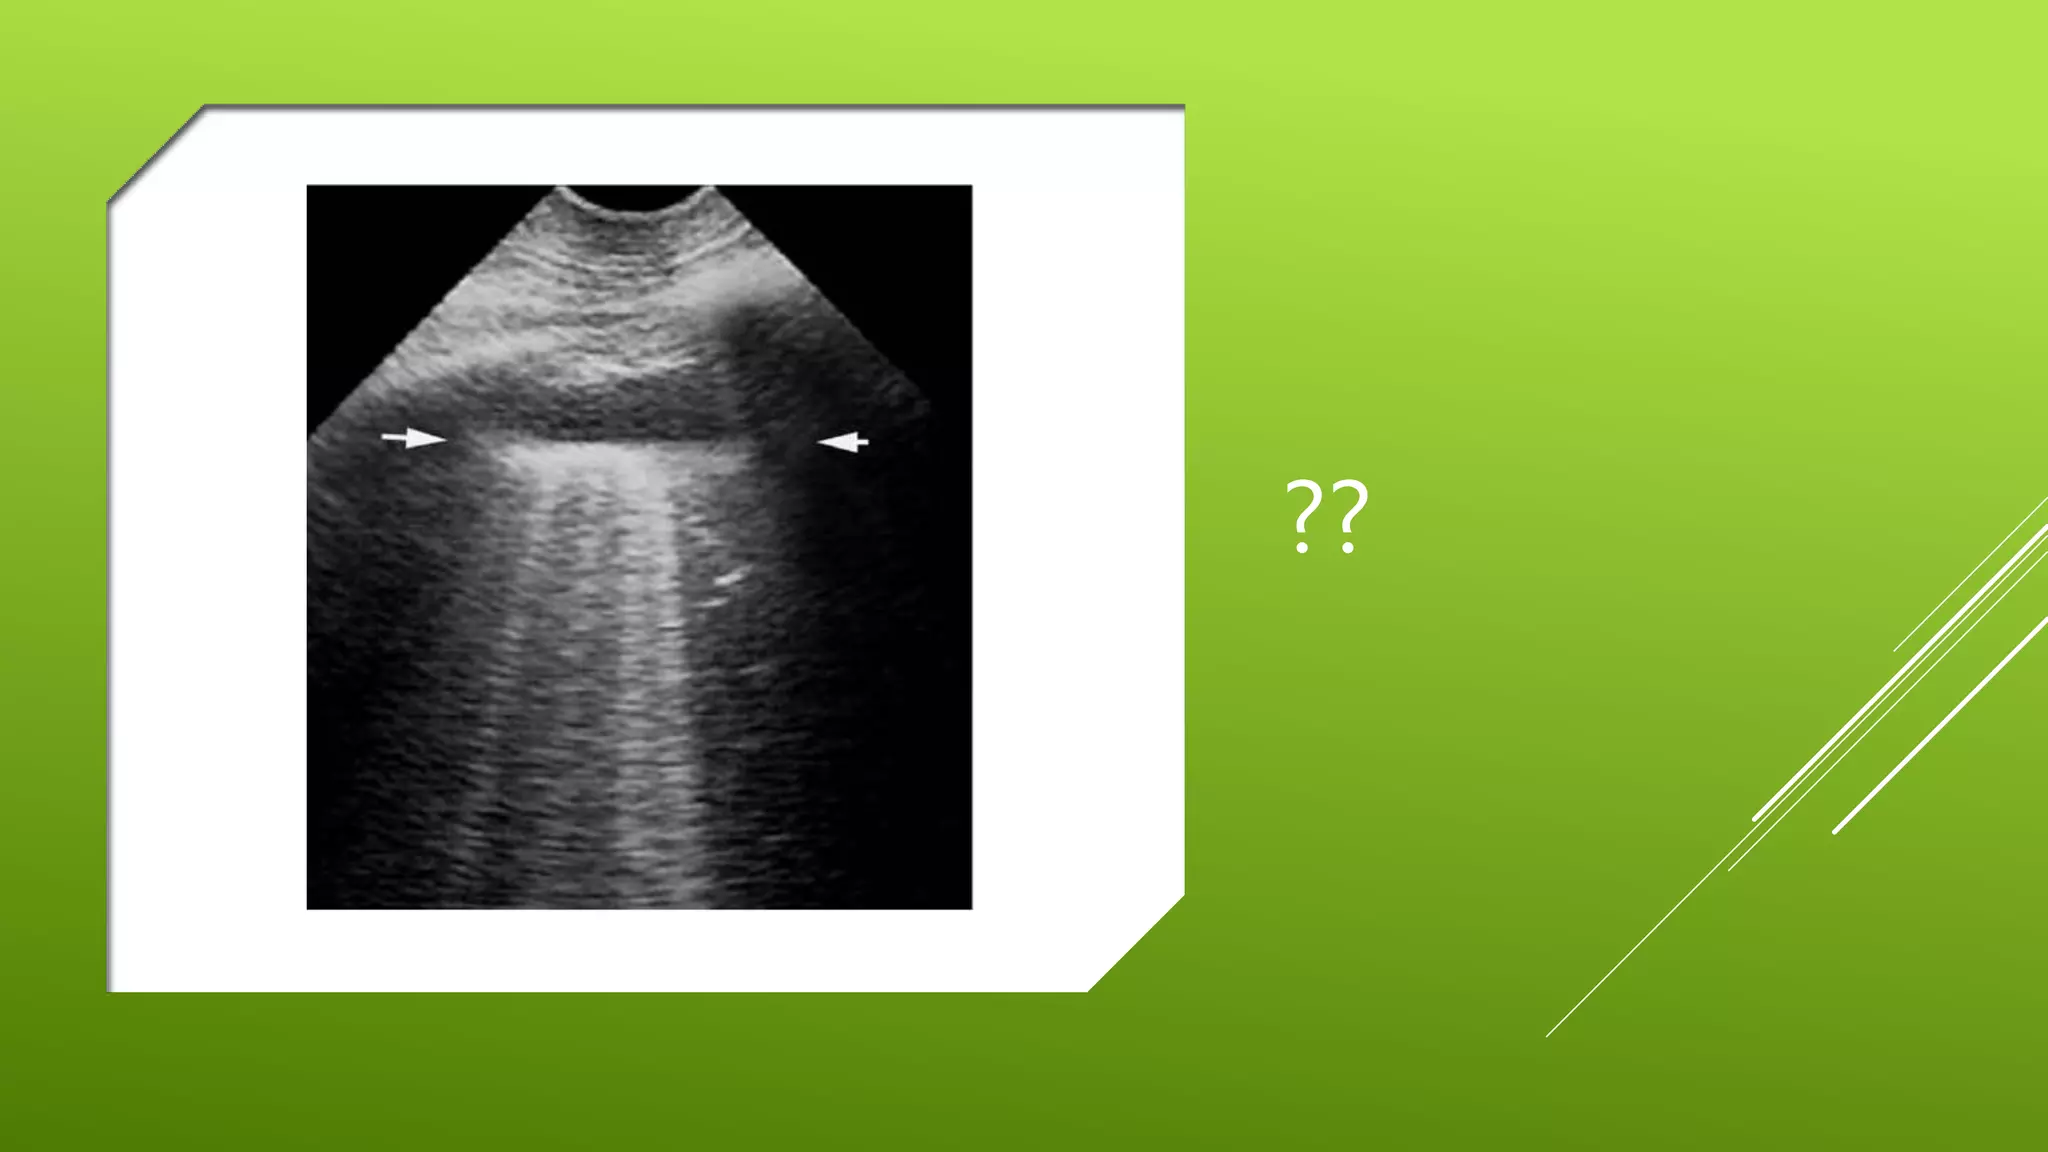

This document contains a series of radiology-related questions and prompts seeking identification and interpretation of various imaging findings, patient presentation details, monitoring values, scoring systems, diagnoses, and management steps. Specific topics include identifying x-ray and CT scan findings, interpreting EKG results, recognizing arrhythmias, assessing intubated and post-surgery patients, and evaluating compliance with treatment plans.